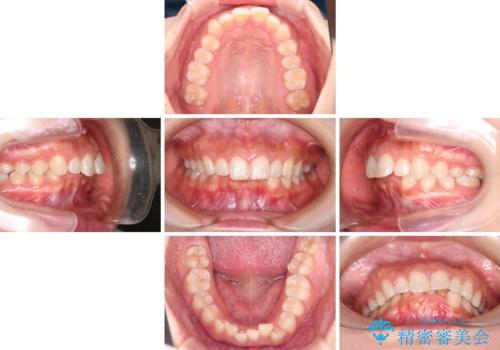

- 上の前歯の出っ歯と前歯の深い咬み合わせを治したいとのことで来院された患者様です。

上顎の歯は後方移動とIPR(歯と歯の間を削る)によって口元が引っ込むように、下顎は歯列全体の拡大とIPRによって上顎とバランスよく咬み合うように設計し、インビザラインにより治療を行うこととしました。

上顎歯列の後方への移動量が多く、右側の奥歯の咬み合わせを改善する必要もあったため、治療には長期間を要しました。